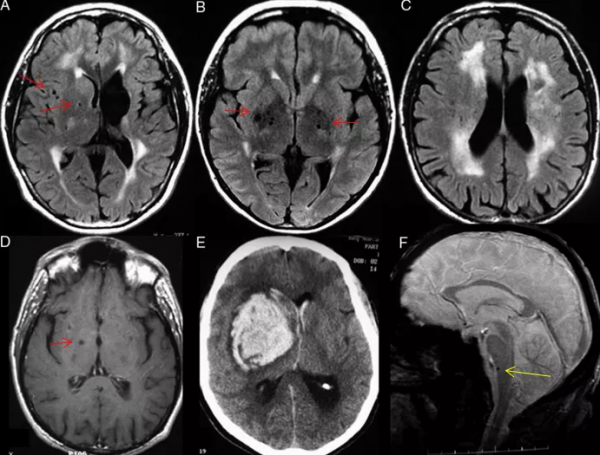

COL4α1突變攜帶者有著各種各樣的MRI表現,包括腦空洞、WMH(主要發生在後腦區)、ICH(通常在圍產期)、短暫性腦缺血發作、腦(尤其是腔隙性)梗死、EPV、CMBs、頸動脈竇瘤和腦動脈瘤(通常累及頸動脈虹吸段)。

半數以上的患者都有CMBs,位於深白質、深灰色核、腦幹和小腦。一些罕見的COL4α2突變病例MRI表現與COL4α1突變相似(圖6)。

圖6 COL4α1突變家系:(A)35歲男性患者,腦室擴張,瀰漫性腦白質病變,基底節區少許圓形低訊號提示EPVS;(B-C)患者47歲姐姐,瀰漫性腦白質病變,基底節區圓形低訊號提示EPVS;(D-E)患者40歲弟弟,基底節EPVS(D)和深部腦出血(E);(F)患者74歲父親腦幹1處微出血。(紅箭頭:EPVS,黃箭頭:微出血)